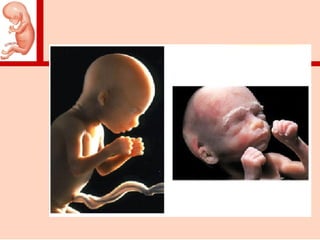

• Período embrionário (embrião)

–Fertilização até a 8ª sem (56 dias)

• Período fetal (feto)

–8ª sem (57 dias) até o nascimento

Embrião → Feto (8 semanas)